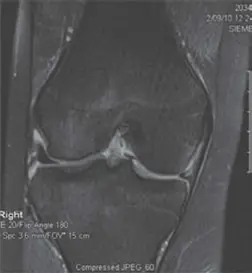

- الرنين المغناطيسي (Magnetic Resonance Imaging - MRI):

- يعتبر الرنين المغناطيسي هو المعيار الذهبي لتشخيص تمزقات الغضروف الهلالي. يوفر صورًا مفصلة للأنسجة الرخوة في الركبة، بما في ذلك الغضاريف الهلالية، الأربطة، الأوتار، والغضاريف المفصلية.

- يستخدم الدكتور هطيف قراءات الرنين المغناطيسي لتحديد موقع التمزق، حجمه، شكله، ومدى استقراره بدقة عالية، مما يساعد في التخطيط للعلاج.